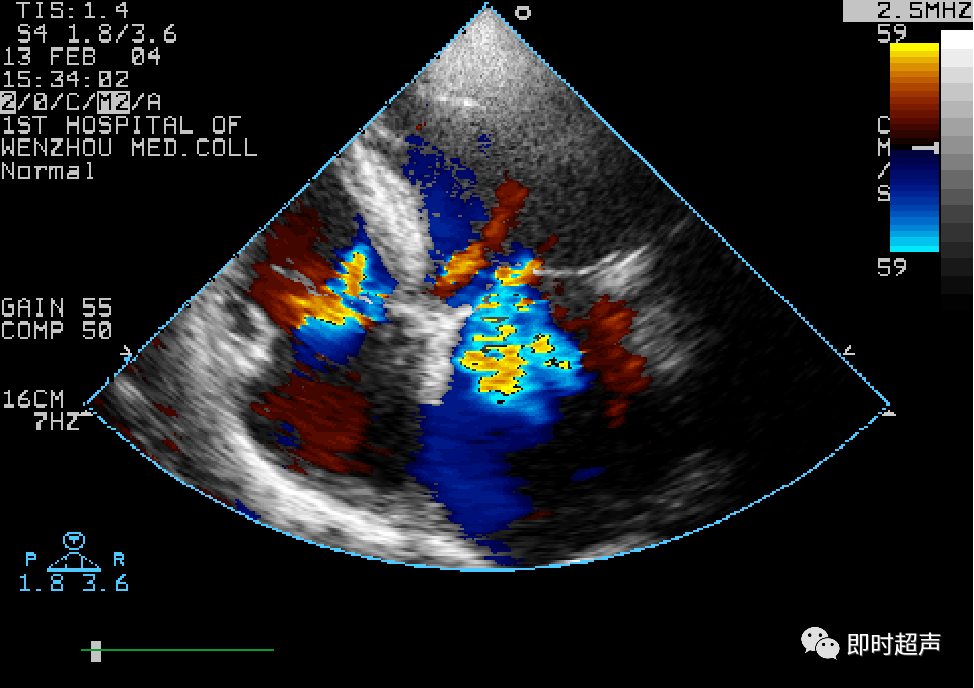

- 二尖瓣口血流速度明显增快。彩色多普勒血流显像显示舒张期二尖瓣口五彩射流束。